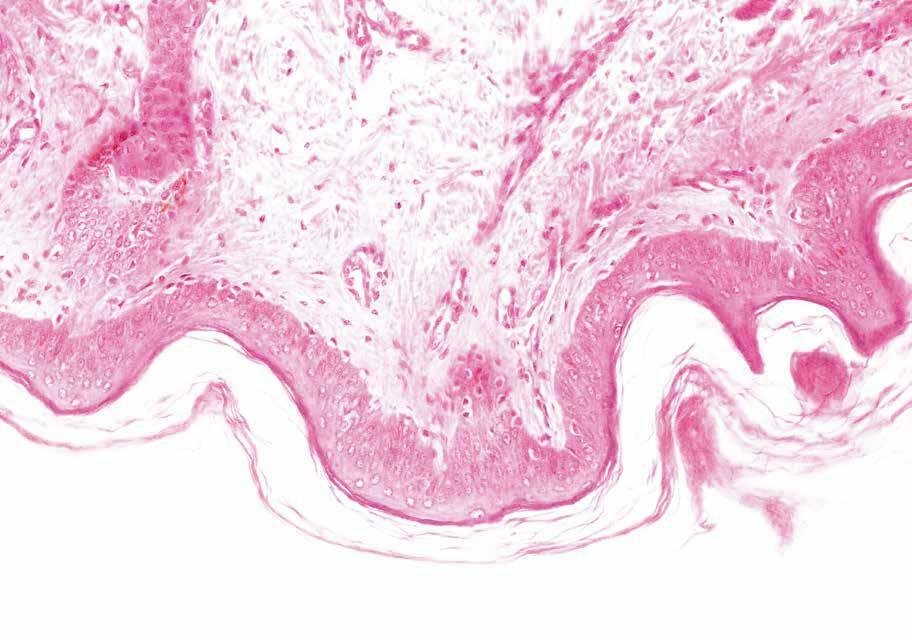

Informatie uit spierweefsel

Een unieke activiteit binnen het NMRC is de analyse van spierbiopten: daarbij wordt een stukje spierweefsel microscopisch onderzocht, onontbeerlijk voor de diagnose van spierziekten. ‘Wij zijn een van de weinige centra in België die dat doen’, zegt Baets. ‘Het is dan ook een dure en tijdrovende activiteit. We doen die analyses in het onderzoekslaboratorium van de Universiteit Antwerpen.’

Spierbiopsieën zullen nog belang rijker worden naarmate er meer experimentele behandelingen voor spierziekten komen, verwacht Baets. ‘Dan zal het immers nodig zijn om het effect van de behande ling te evalueren aan de hand van spierbiopsieën.’